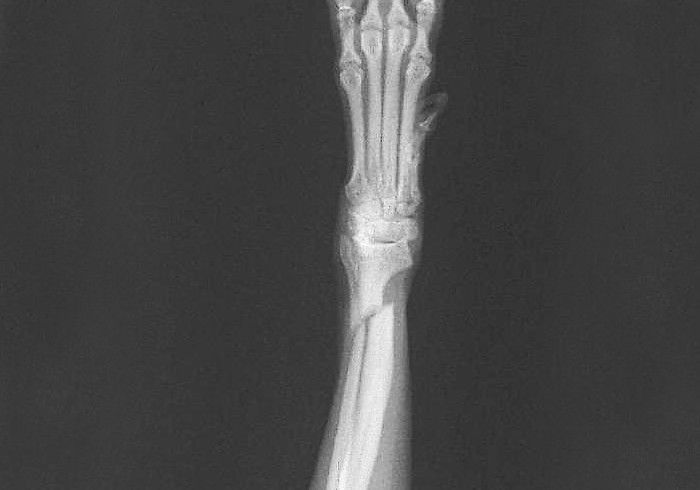

橈尺骨骨折

ソファーやイス、抱っこされた状態から落下するなどして、前肢の橈尺骨を骨折するケースがあります。トイプードルやチワワ、ポメラニアンなどの小型犬やイタリアン・グレーハウンドなどの骨が細い犬種にみられやすい骨折です。

プレート固定法やピンニング法、創外固定法など、症例に合わせた治療法を選択します。当院は、従来のプレート法よりも強固で安定性のあるインターロッキングシステムのSOP、LCP による治療にも対応しています。